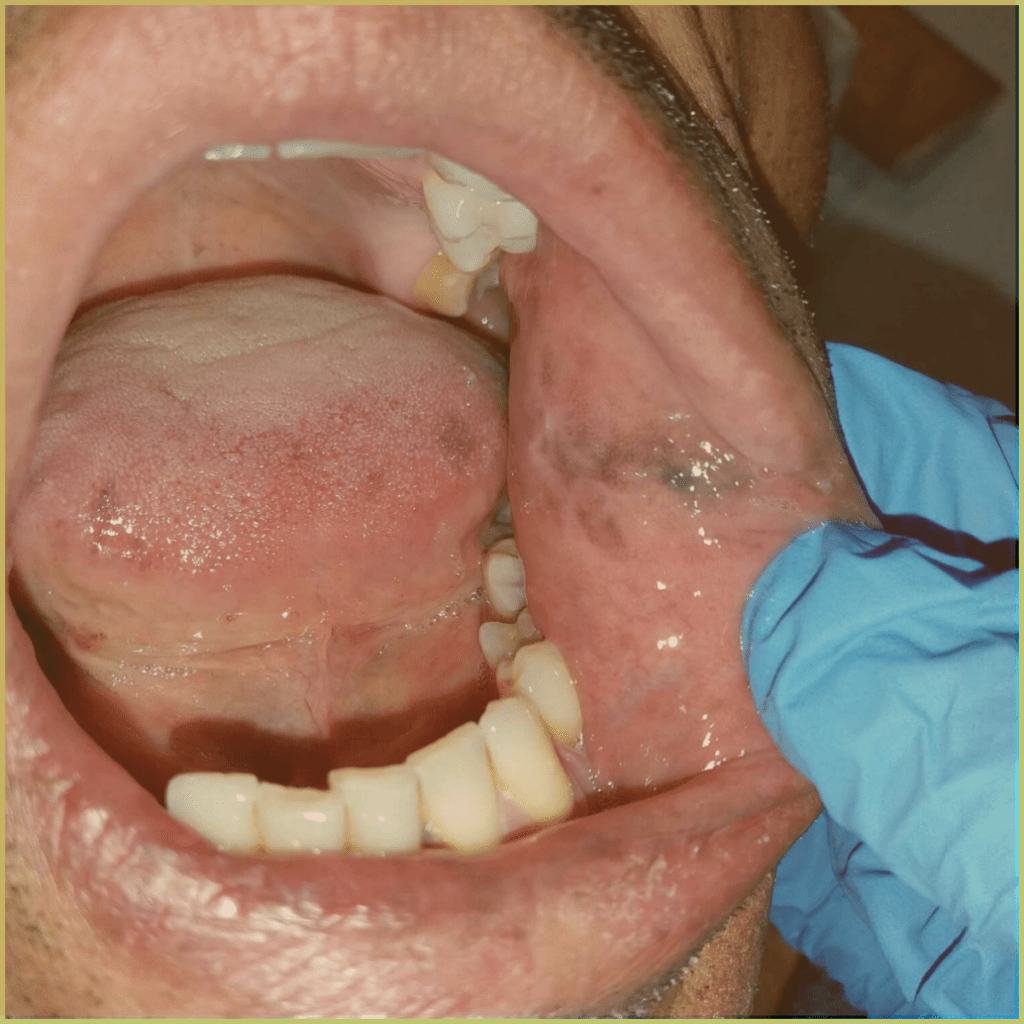

AMALGAM TATTOO

Amalgam Tattoo refers to the discoloration seen in oral tissues where dental amalgam has been deposited. The common clinical presentation includes:

- Well differentiated gray, blue or black focal macule.

- Asymptomatic lesions with no indication of associated inflammation.

- May be visible radiographically.

Diagnosis is based on the lesion history, clinical presentation, and radiographic analysis only. If biopsied, microscopic findings may include:

- Fragments of metal within connective tissue.

- Metal staining of reticulin fibers.

- Particles may be surrounded by fibrous tissue.

- Granulomatous inflammation with a mixture of lymphocytes and plasma cells.

Your differential diagnosis should include:

- Melanoma.

- Vascular malformation.

- Nevus.

- Mucosal melanotic macule.

- Melanoacanthoma.

No treatment is required.